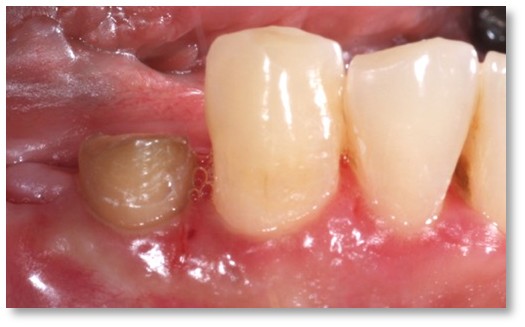

![]() | ![]() |

| Before and after surgery to reshape gums | X-ray showing results before and after bone graft surgery |